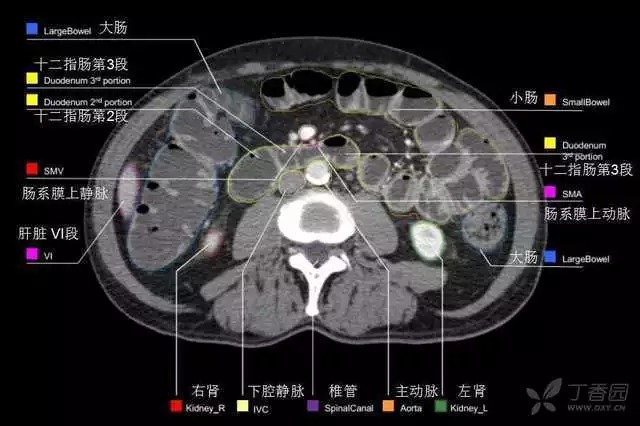

腹部肝脏高清CT断层的图谱

全腹部高清CT图谱,淋巴结彩色图谱,血管解剖图谱大汇总!